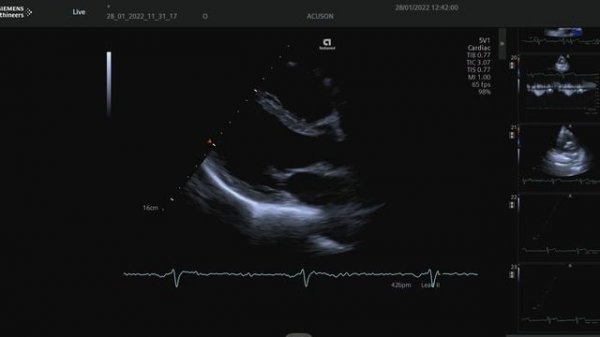

US_ACUSON Redwood.mp4